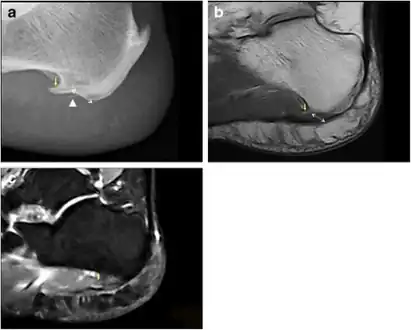

A radiograph showing osteophytes on the posterior and inferior aspects of the calcaneus

An inferior calcaneal spur is located on the inferior aspect of the calcaneus and is typically a response to plantar fasciitis over a period, but may also be associated with ankylosing spondylitis (typically in children). A posterior calcaneal spur develops on the back of the heel at the insertion of the Achilles tendon.[2]

An inferior calcaneal spur consists of a calcification of the calcaneus, which lies superior to the plantar fascia at the insertion of the plantar fascia. A posterior calcaneal spur is often large and palpable through the skin and may need to be removed as part of the treatment of insertional Achilles tendonitis.[2]